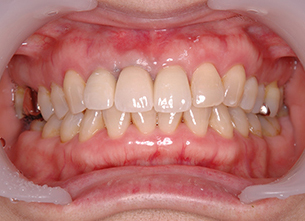

症例1 : 上下顎無菌顎症例

69歳、男性。

• 上顎は両側サイナスリフトと同時に即時荷重を行った。

• 下顎は抜歯即時埋入即時荷重を行った。

• 最終補綴物は、チタンのP.I.B.とM.B.のコンビネーションで修復した。

• 本症例の要旨は第39回日本口腔インプラント学会(大阪)にて症例報告した。